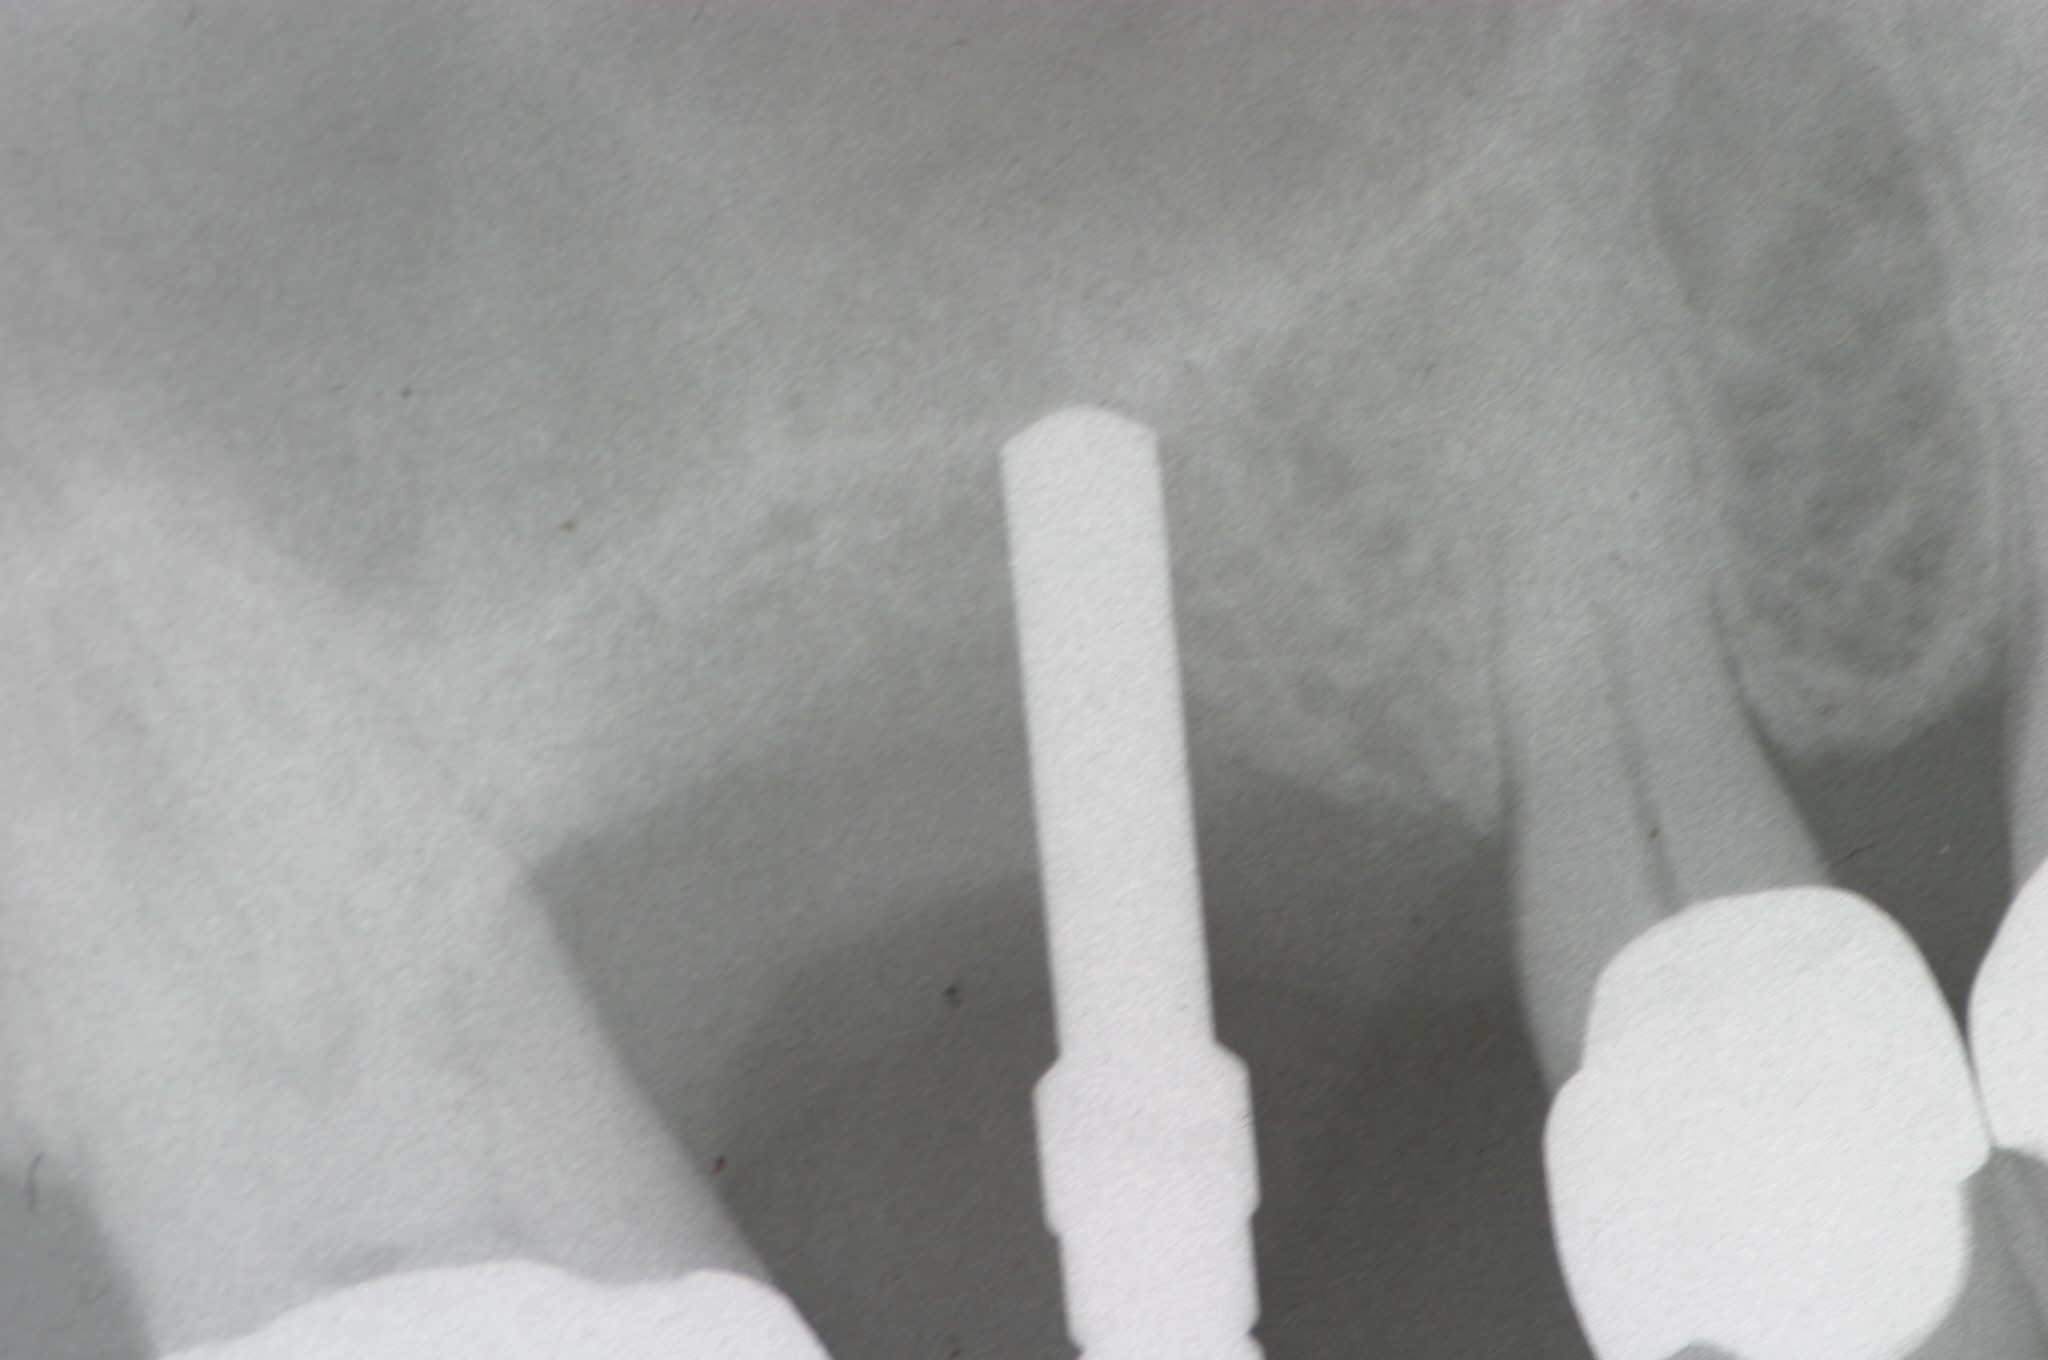

Day of sinus augmentation and implant placement in the No. 3 position. The sinus membrane has been raised about 7 mm to 8 mm.

Fig. 21

CBCT scan (Kodak 9000D) of No. 3 area, day of placement. Appearance of native bone and bone graft is clearly discernable.

Fig. 22